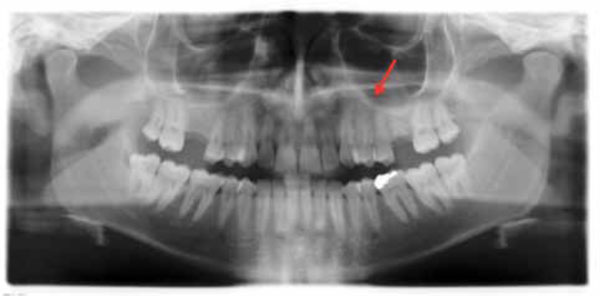

Ortopantomograph, thirty months after surgery, showing the intact bone in the left premolar maxillary area.

The lesion healed uneventfully, without clinical and radiological signs of recurrence at 30 months follow up. (Figs. 3, 4).